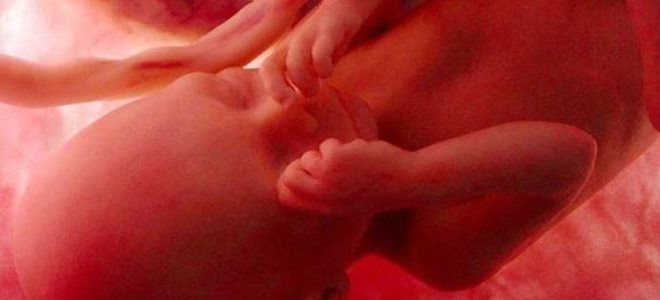

Как выглядит плод на 29 неделе беременности?

На 29-й неделе беременности внешний вид будущего малыша претерпевает значительные изменения. Лануго, тонкий волосяной покров, который защищает ребенка и участвует в терморегуляции, почти полностью исчезает с его кожи. Увеличивается толщина подкожно-жировой клетчатки, что придаёт ребенку более округлые формы. Также формируются кожные складки, особенно заметные на бедрах и ягодицах.

Волосы на голове становятся длиннее и начинают приобретать свой окончательный цвет. Черты лица становятся более выраженными, и при внимательном взгляде можно заметить, на кого из родителей малыш больше похож. Радужная оболочка глаз начинает окрашиваться, что можно увидеть на цветном УЗИ. Уши занимают своё естественное положение.